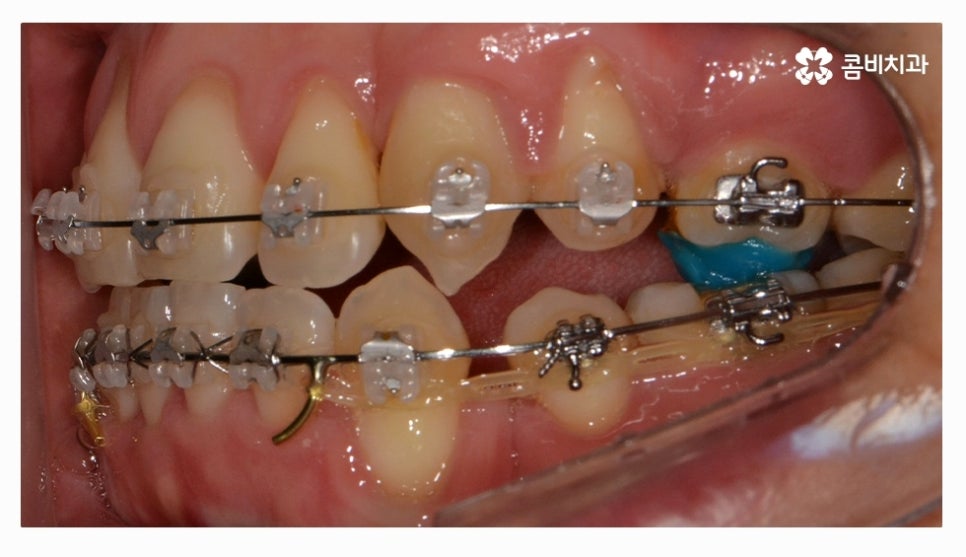

오늘 소개드릴 환자분은 윗니와 아랫니가 제대로 맞물리지 않는

부정교합 사례이며 클리피씨교정을 통해서 치료가 진행된 사례라고 할 수 있어요.

전체교정을 하시는 분들의 경우 보편적으로 많이 선택하시는

교정 장치는 클리피씨교정이라고 할 수 있을 정도로 선호도가 높으며

클리피씨교정은 자가 결찰 장치로 통증 감소 및 교정 기간을

단축시킬 수 있으며 관리가 편리하다는 장점도 갖고 있어요

클리피씨교정은 세라믹 재질이기 때문에 심미적으로도 우수한 편이며

브라켓과 와이어 고정을 위한 철사를 사용하지 않기 때문에 철사로 인해 찔리거나

입안이 뜯겨 피가 나는 경우를 예방할 수 있는데요.

클리피씨교정은 철사를 쓰지 않고 특수 클립이 내장되어

클립을 이용하여 와이어를 고정하고 열고 닫을 수 있기 때문에

교정 장치로 인한 불편함이 줄어들 수 있으며 철사를 사용하지

않는 것만으로도 보다 편안함을 느낄 수 있지만 치아를 적은 힘으로

지속적으로 이동시켜서 상대적으로 통증이 적고 치과 내원 횟수도 줄일 수 있어요.

위 환자는 총 치료기간 약 30개월이 소요되었으며

개인에 따라 치료 기간 및 결과가 차이가 있을 수 있고,

개인에 따라 출혈 및 부작용이 발생할 수 있습니다.